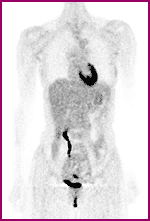

La disbiosi

La disbiosi è “semplicemente” l'alterazione dell'equilibrio della flora batterica.

In queste condizioni gli stessi bacilli della flora diventano dannosi.

Producono un eccesso di ammoniaca che può intossicare fegato e cervello.

Formano le nitrosamine che inducono il cancro nello stomaco e nell’intestino. Generano prodotti cancerogeni a partire dagli azotati dei coloranti alimentari, modificano l’assetto ormonale dell’asse gonadico (sessuale), con rischio di cancro alla mammella, fino ad aumentare il tasso di colesterolo e più propriamente il rischio cardiovascolare.

La disbiosi può causare lesioni alla parete intestinale, che lascia passare nel sangue le sostanze tossiche, genera forti squilibri a livello neurovegetativo (quindi nella nostra centralina di comando) e a livello immunitario.

Una forma particolare di disbiosi è quella legata alla trasformazione in parassita della candida albicans.

È facile comprendere che questi danni si propagano rapidamente a tutto l'organismo, fino a danneggiare le funzioni o gli organi più deboli del soggetto.